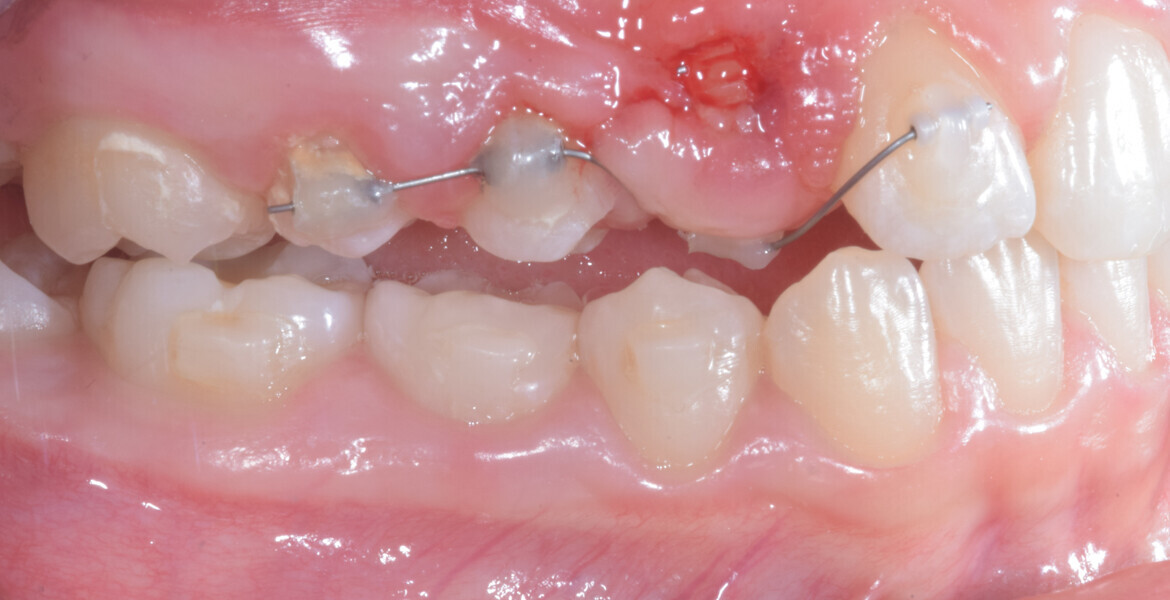

At the end of the first stage of aligner treatment (Figs. 20–24), the auxiliary phase began with the bonding of two MTAs on the maxillary right premolars. A 0.016-in Australian archwire, shaped into a cantilever configuration, was then inserted into the MTAs, and a cutout was created on the final aligner. To prevent rotation, the archwire was cinched distal to tooth #15 and the cinch covered with composite.

At the same time, the impacted canine was exposed by laser, a button was bonded on to it and the cantilever was connected to the button using an elastomeric thread. The final aligner was used for space maintenance while the cantilever was reactivated until the canine had erupted (Figs. 25–27). After complete eruption, further MTAs were bonded on the canine and on the lateral incisor, and a 0.014 in. NiTi archwire was used to finalise the eruption (Figs. 28–30). Only at the end of the forced eruption phase did the further aligner stage take place, aimed at achieving an ideal Class I relationship on the right by maxillary right mesialisation using Class III elastics and 27 maxillary aligners and 13 mandibular aligners (Figs. 31–33).